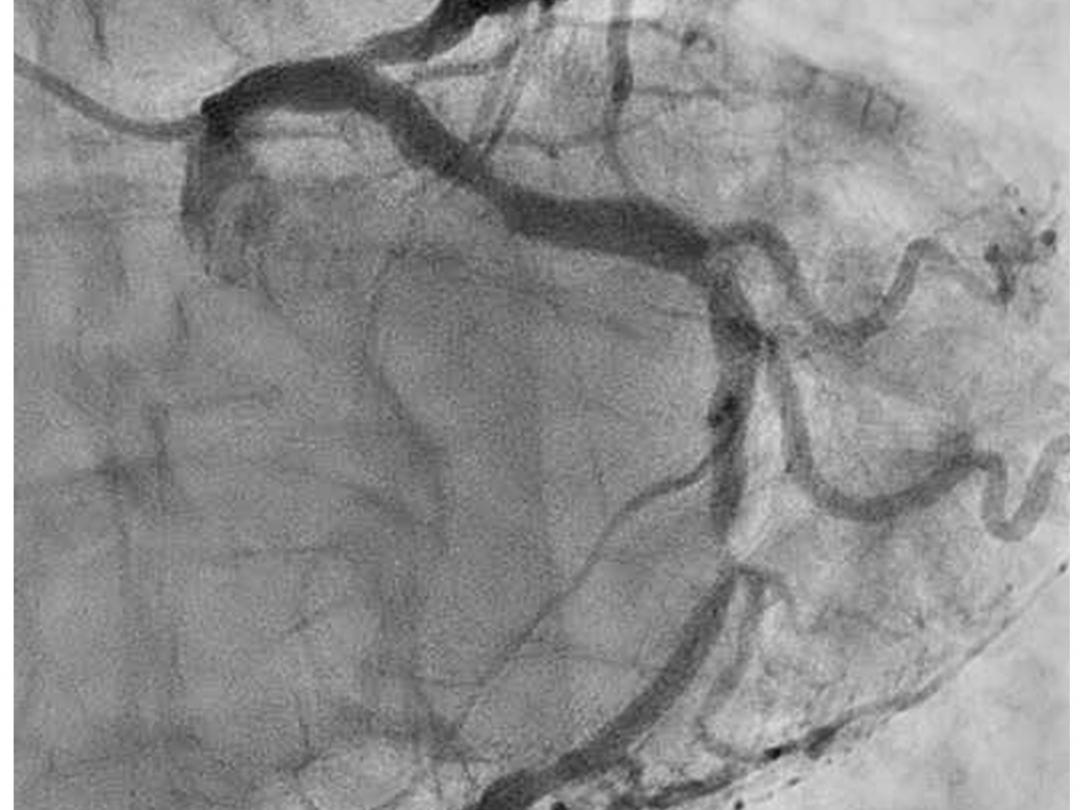

Angiogram van de A. coronaria sinistra.

Een 86-jarige man met gekende arteriële hypertensie wordt verwezen vanwege een lang aanslepende eructonesius. Aanvankelijk betrof het een geïsoleerde klacht, alleen uitgelokt door inspanning, maar na verloop van tijd ontstond deze ook in rust. Gastro-intestinale controle bleek geruststellend. Pas nadat er ook retrosternale klachten met uitstraling naar de linker arm ontstonden, werd de patiënt voor cardiologische controle verwezen. Hierbij werd een kritische stenose van de ramus circumflexus vastgesteld. Na angioplastiek was de patiënt klachtenvrij.